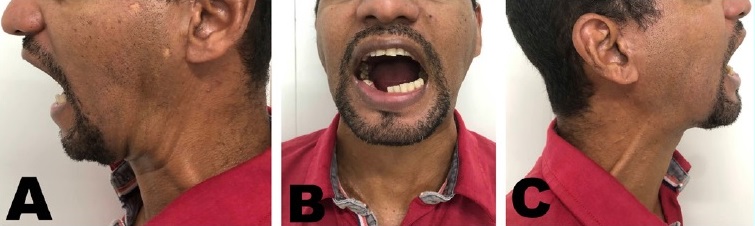

The patient remained hospitalized in the unit until the third postoperative day (POD). During this period, he was on antibiotic therapy with Ceftriaxone 1g 12/12, analgesia, and venous anti-inflammatory. He was discharged on the fourth POD, with oral prescription. On the 15th POD, all skin sutures were removed, with no signs of inflammation. The patient maintained physical therapy, pain management medications, and active mobilization. At the 9-month follow-up, the patient was asymptomatic, with 23 mm of interincisal opening and no signs of recurrence (Figure 5).

TMJ ankylosis is a pathology that modifies anatomy and function. It is generated by the growth of bone and fibrous tissues that cause a gradual loss of function.2 Patients affected by this process present limitations in mouth opening, mandibular hypomobility, and facial asymmetry, often characterized by deviation of the chin to the affected side.5,6In the present report, the patient had a severe opening limitation with a 12-mm interincisal distance, dental malocclusion, and limited mandibular excursions.